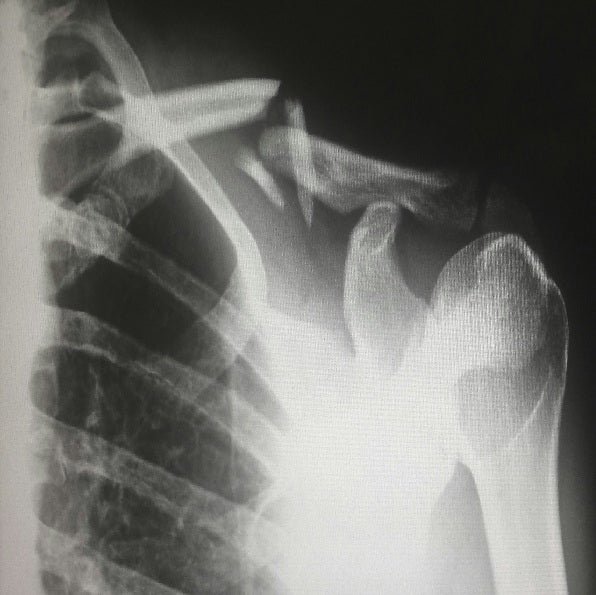

Frakturen

In einer umfangreichen Literaturrecherche im Jahr 1992 fand Gossling [3] insgesamt 44 Studien zur Anwendung pulsierender Magnetfelder bei Tibiafrakturen (Bruch des oberen Abschnitts des Schienbeinknochens).

Dabei wurde festgestellt, dass die Heilungsrate bei Verwendung der Magnetfeldanwendung bei 81% lag, verglichen mit 82% bei chirurgischen Eingriffen. Dies ist besonders bemerkenswert, da in vielen Fällen ohne chirurgische Behandlung keine Heilung möglich ist.

- 🐭 In einer Studie mit 20 Versuchstieren wurde eine einfache Blindstudie durchgeführt. Die Tiere erhielten eine neuntägige Behandlung für eine Fraktur. Das Ergebnis zeigte eine signifikante Beschleunigung der Heilung im Vergleich zur Placebogruppe.

- 📋 In einer zweiten Studie mit 13 Patienten wurden nicht operativ versorgte Frakturen untersucht. Dabei wurde eine Magnetfeldstärke zwischen 10 und 100 µT angewendet. Das Ergebnis zeigte, dass 11 Frakturen vollständig geheilt waren. Bei den zwei nicht zusammengewachsenen Frakturen betrug der Abstand zwischen den Knochenenden nur noch 1 cm.